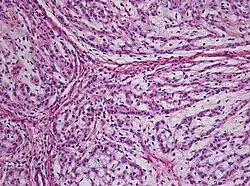

Chordome sind langsam und destruktiv wachsende Tumoren der Wirbelsäule und der Schädelbasis, die in etwa 10 % der Fälle metastasieren.

Chordome werden manchmal zu den Knochentumoren gezählt, obwohl sie nicht aus Knochengewebe stammen, sondern aus Resten der Chorda dorsalis (Notochordoa) an den Enden der Wirbelsäule. Damit lassen sich auch ihre Hauptlokalisationen, nämlich Schädelbasis und Steißbein, erklären. Die ICD-O-3 klassifiziert sie unter die Sonstigen Tumoren des Nervensystems (Nr. 937).